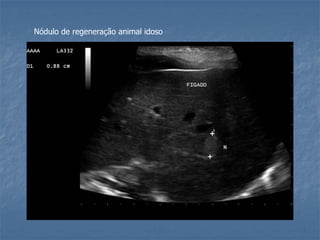

Nódulos de regeneração em animal idoso

Nódulo de regeneração animal idoso